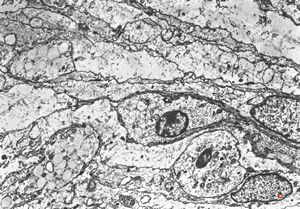

F,50y. | progressive multifocal leukoencephalopathy- viral particles in a glial cell

F,50y. | progressive multifocal leukoencephalopathy- viral particles in a glial cell

F,50y. | progressive multifocal leukoencephalopathy- viral particles in a glial cell